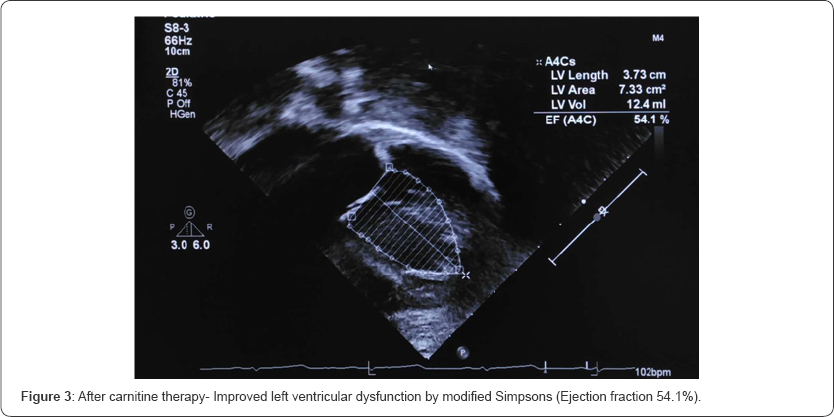

Her initial echocardiogram revealed severe depressed LV dysfunction- Ejection Fraction (EF) by modified Simpsons {24.3%}, M mode EF {24.2%} (Figure 1 &2). In relation to her hypertension related to end-stage renal failure, she is maintained on angiotensin-converting enzyme inhibitors. Further, she was investigated for carnitine levels which confirmed secondary carnitine deficiency (Table 1). After the 6 months trial of 20mg/kg of intravenous carnitine for 5 times a week (end of dialysis) leads to remarkable improvement in IH episodes and cardiac function. Her repeated echocardiogram revealed improved LV function- modified Simpsons {54.1%}, M mode EF {50.4%} (Figure 3 & 4).